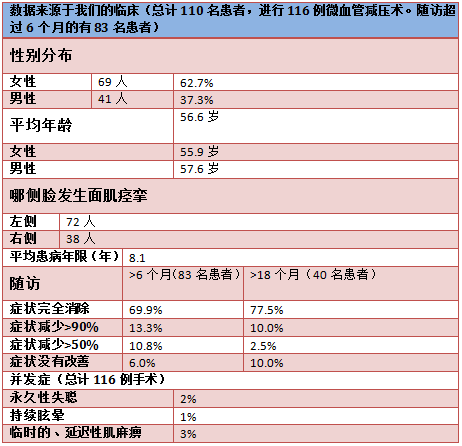

文献报道微血管减压术术后第一年的平均成功率为80%-88%[14,18,19]。这与米兰·(milan)的临床试验结果相符(table)。随访结果显示,6个月的手术成功率(手术成功指肌痉挛减少90%以上)为83%,18个月为87%。在症状改善有限或根本无效的病人中,手术不成功的主要原因是独特的解剖结构,如大直径静脉、动脉位于面神经和前庭蜗神经之间、极细长和在狭小的髓周空间里膨胀的椎动脉[14,18,19]。

和其他任何外科手术一样,微血管减压术也存在一定的手术风险。主要风险是短暂的或永久性的听力损伤,甚至造成单侧失聪。据报道,在一些规模较大的临床研究中风险为1.5%-8%[14,18-21]。永久性的面神经麻痹的风险为0.7%-0.9%[9,22]。延迟的面神经麻痹更普遍(病例数的3%-8%)。术后面神经的起初功能完整。但是,在平均12天之后,手术一侧的面神经可能会突发急性的高水平的麻痹。与之相关的一个可能的原因是带状疱疹的激活。然而,到目前为止,面神经的延迟麻痹的病原学还未确定[22]。几乎所有患者都会随着时间症状逐渐消失。微血管减压术围手术期危及生命的风险(如占位出血、小脑或脑干梗塞)小于1%。米兰·(milan)在临床上还未遇到这样的病例。总之,米兰·(milan)可以认为该方法成功率高,风险水平是可接受的。事实上,患者因该手术疗法得以长期免除疾病的痛楚。

TABLE